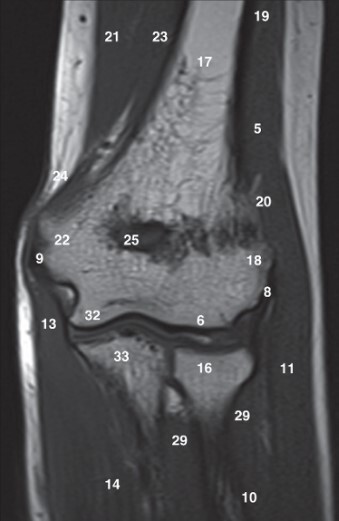

Label 6,16,17,18,22,25,32

6=Capitulum of lt. humerus

16=Head of lt. radius

17=Lt. Humerus

18=Lateral condyle (lt. humerus)

22=Medial condyle (rt. humerus)

25=Olecranon fossa of lt. humerus

32=Trochlea of lt. humerus